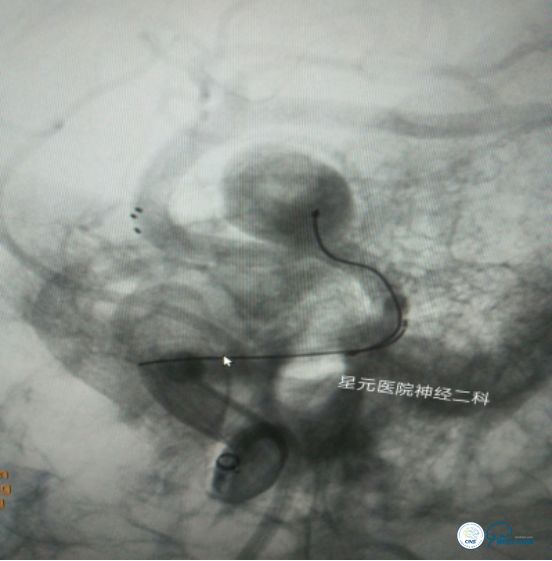

方案二:双支架辅助弹簧圈栓塞技术

➤双导管、双支架同时释放,保证M2段主干及瘤体所发出的眶额支通畅。

➤通过微导管A回收支架。将微导管A缓慢退至大脑中动脉M1段(中部),在0.014微导丝的导引下进行超选M2段主干,将微导管A头端对应瘤体9点钟方向,后通过微导管A将支架缓慢半释放到预定位置,保证支架尾端至于大脑中动脉M1段远端。

➤根据需要进行微导管B的头端蒸汽塑形,在微导丝的导引下将微导管B缓慢送至瘤腔内,进行侧枝开口的超选。多次尝试、反复超选,因侧枝开口与瘤体成角太锐而超选失败,随之放弃该方案。